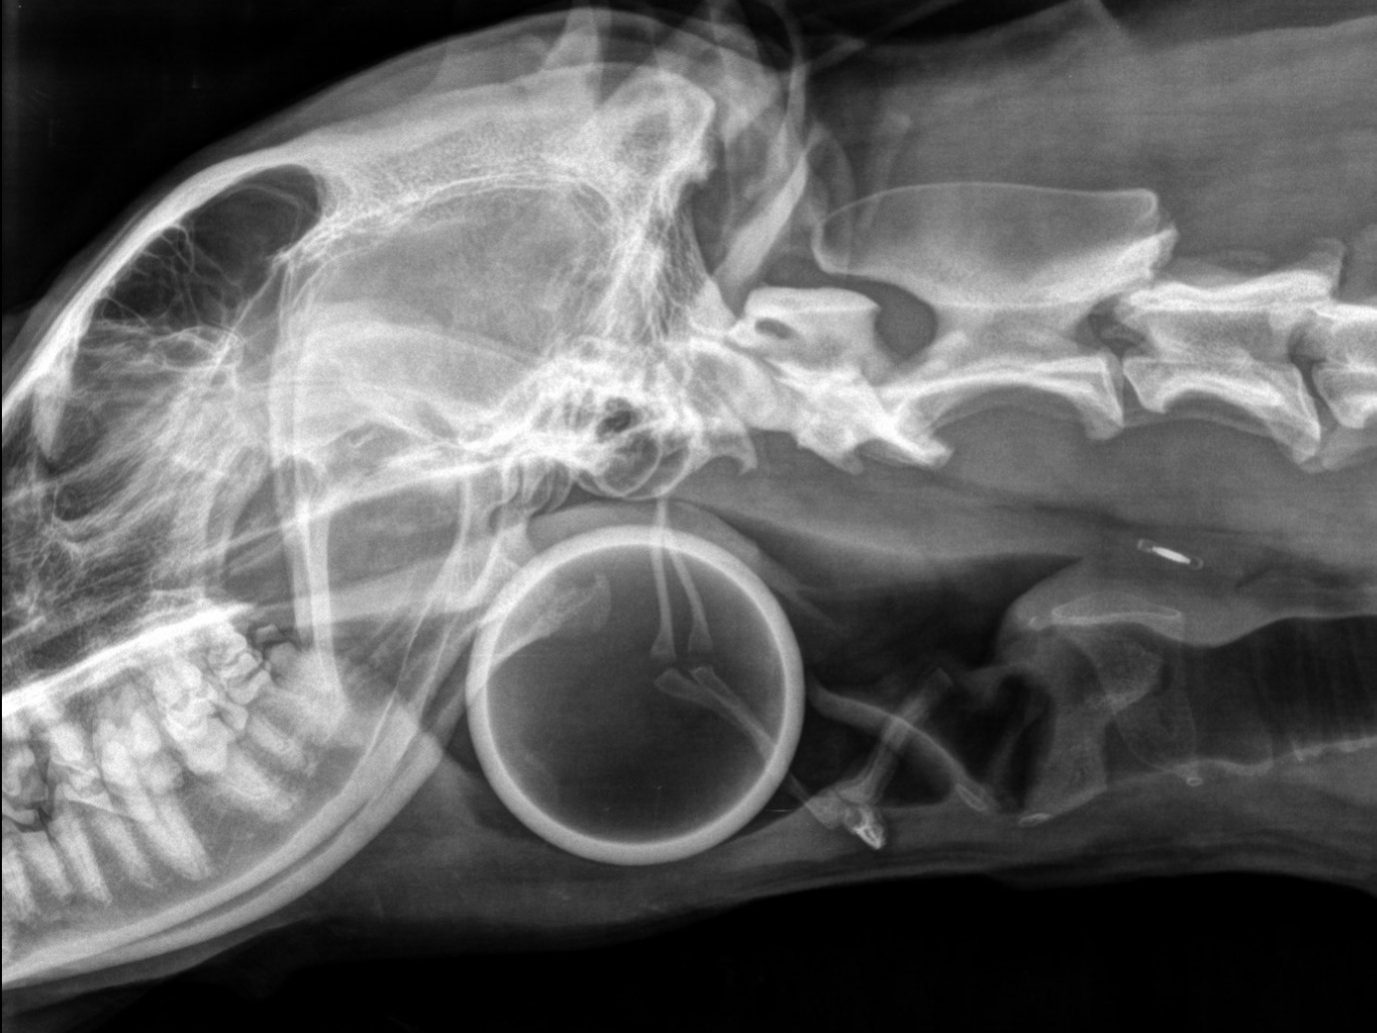

La radiographie :

la région pharyngée montre la présence d’un corps étranger circulaire de 6,7cm de diamètre à l’entrée de la trachée.